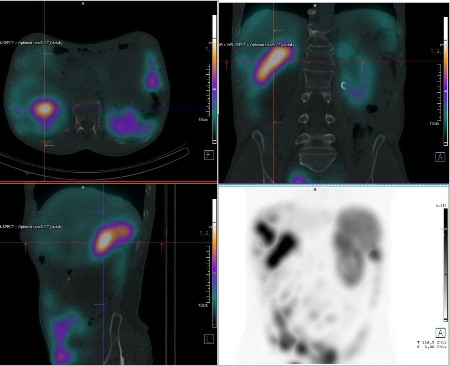

/ Obr. č. 6: Fúze SPECT/CT břicha a pánve 4 hod. po aplikaci OctreoScanu.

/

Pozorujeme patologicky zvýšenou depozici radiofarmaka: nejméně čtyři ložiska v pravém jaterním laloku (ložisko s vysokou akumulací laterálně, největší ložisko vysoce akumulující oválného tvaru dorzokaudálně, další dvě malá dorzolaterálně a kraniálně), vícečetná drobná ložiska v břiše a pánvi, zřejmě v uzlinách mezenteria a na peritoneu, ložisko pod dolním okrajem sleziny.

Akumulace dále ve slezině, ledvinách a střevních kličkách představuje fyziologickou distribuci. Vedl. nález obrovská hydronefróza pravé ledviny bez akumulace.

Mnohočetná ložiska patol. depozice Octreotidu odpovídají generalizaci procesu v dutině břišní - játra, mezenterium, karcinomatoza peritonea, pod slezinou.